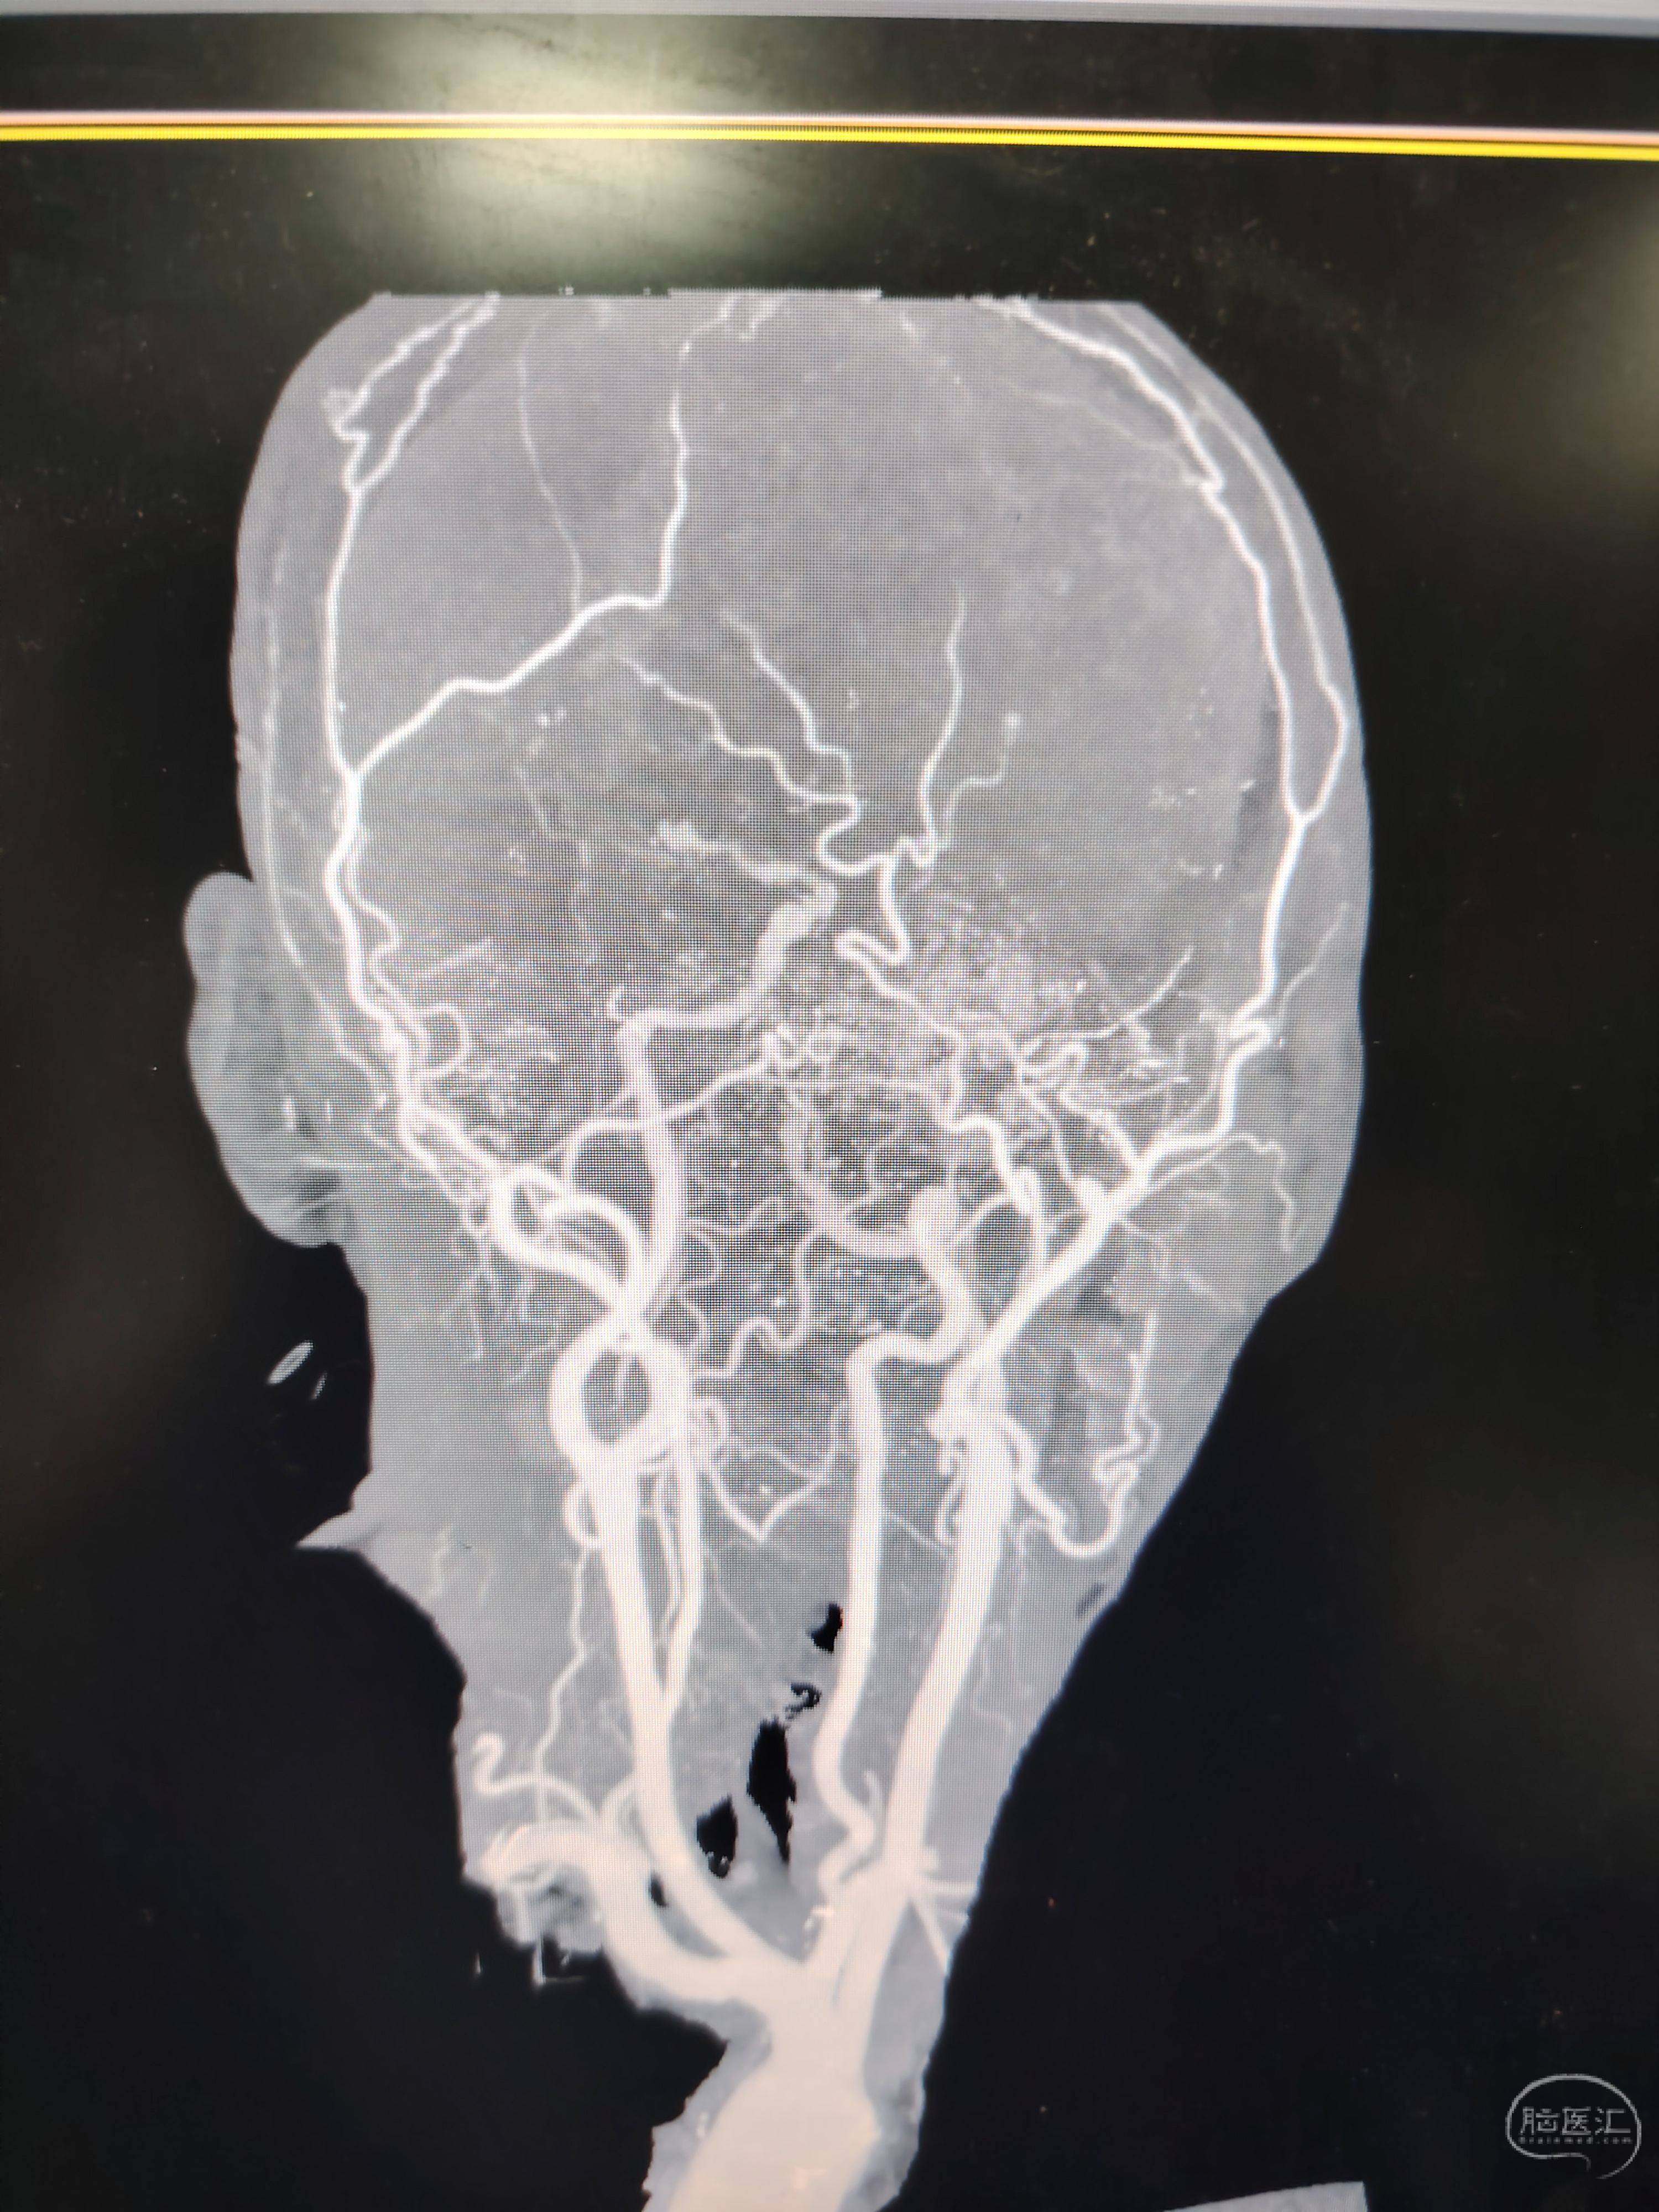

发病前MRA示颅内多发动脉瘤。

急症CTA颅内血管不显影。